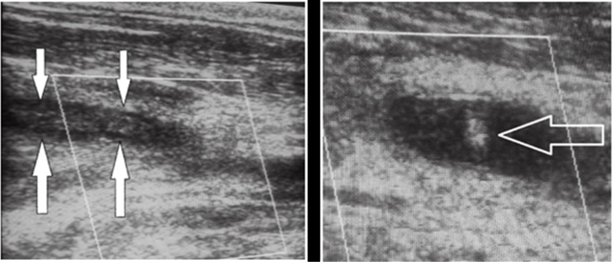

Figure 3: echo-doppler cervical: extensive thrombosis of the right jugular vein and multiple cervical adenopathies.